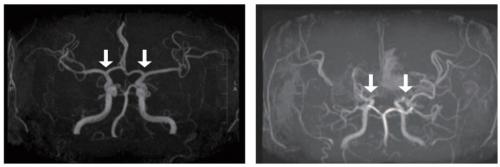

(¿ÞÂʺÎÅÍ) Á¤»ó ¹× ¸ð¾ß¸ð¾ßº´ ȯÀÚÀÇ ³úÇ÷°ü

¸ð¾ß¸ð¾ßº´Àº Ưº°ÇÑ ¿øÀÎ ¾øÀÌ ´ë³ú¿¡ Ç÷¾×À» °ø±ÞÇÏ´Â ³»°æµ¿¸ÆÀÇ °¡Áö Ä¡´Â ºÎÀ§ Ç÷°üÀÌ ¼­¼­È÷ Á¼¾ÆÁö´Â ¸¸¼º ÁøÇ༺ ³úÇ÷°üÁúȯÀÌ´Ù. ÀÌ·Î ÀÎÇØ Ç÷·ù°¡ ºÎÁ·ÇØÁö°í, ºÎÁ·ÇÑ Ç÷·ù¸¦ º¸ÃæÇÏ·Á´Â ºñÁ¤»óÀûÀÎ ¹Ì¼¼Ç÷°üµéÀÌ ÀÚ¶ó³ªÁö¸¸, ÀÌ Ç÷°üµéÀº Ç÷¾×À» ÃæºÐÈ÷ °ø±ÞÇÏÁö ¸øÇϰí ÅÍÁö±â ½¬¿ö ³ú°æ»öÀ̳ª ³úÃâÇ÷°ú °°Àº ½É°¢ÇÑ ¼Ò¾Æ ³úÁ¹ÁßÀ» À¯¹ßÇÏ°Ô µÈ´Ù.

Áö±Ý±îÁö ¸ð¾ß¸ð¾ßº´À» È®ÁøÇϱâ À§Çؼ­´Â ħ½ÀÀûÀÎ ³úÇ÷°ü Á¶¿µ¼úÀÌ Ç¥ÁØÀûÀÎ °Ë»ç¿´°í, À̴ ƯÈ÷ ¼Ò¾Æ¿¡°Ô Å« ºÎ´ãÀ» ÁÖ¾ú´Ù. MRI/A¿Í °°Àº ºñħ½ÀÀû °Ë»çµµ ÀÖÁö¸¸, Ç÷°ü ÇùÂøÀÌ °úÀåµÇ°Ô ³ªÅ¸³ª´Â °æ¿ì°¡ ÀÖ°í ³ú±âÀúºÎÀÇ ¸ð¾ß¸ð¾ßÇ÷°üÀ» ÀÚ¼¼È÷ Æò°¡Çϱ⠾î·Á¿ö Á¶±â Áø´Ü°ú Áúº´ÀÇ ÁøÇà »óŸ¦ Á¤¹ÐÇÏ°Ô ÆÄ¾ÇÇÏ´Â µ¥ ÇѰ谡 ÀÖ¾ú´Ù. ÀÌ¿¡ µû¶ó ¾×ü »ý°Ë(Ç÷¾× µî ü¾×À» ÅëÇÑ Áø´Ü)ÀÇ Çʿ伺ÀÌ ²ÙÁØÈ÷ Á¦±âµÇ¾î ¿Ô´Ù.